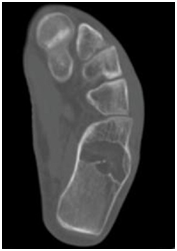

Intraosseous lipomas are diagnosed with plain radiography and CT scan (Figure 1) (Figure 2A) (Figure 2B). Mainstay of treatment is conservative; however surgery is indicated in severe pain not responding to conservative treatment, impending pathological fracture and malignant transformation (Figure 3). Treatment for these tumors is curettage and bone grafting (Figure 4) with good prognosis.8–10

Figure 2b CT Scan of the foot, axial view, showing lytic lesion.